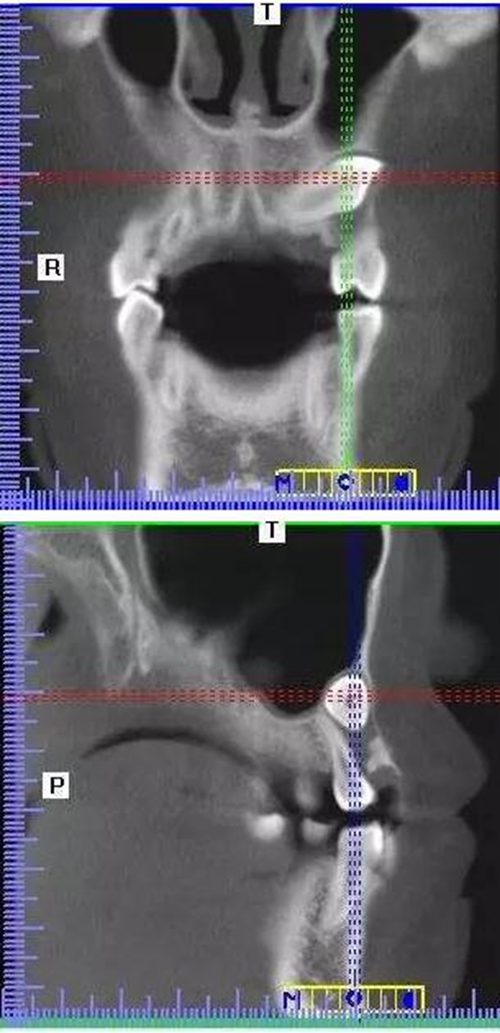

本案:患兒,女,14歲,因牙齒矯正來院,檢查見83滯留,43未見萌出,拍片發(fā)現(xiàn):43埋伏阻生于31、41、42根尖下方,按照正畸診療計劃,擬行43拔除術(shù)。

CBCT顯示